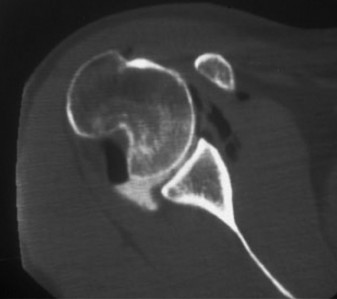

A 45-year-old carpenter presents with shoulder pain that has been ongoing for the last 3 months. He denies any significant injury. He describes night pain and significant discomfort at work. His imaging is shown in Figure 2–9. What is the most likely diagnosis?

🔍 Click to enlargeClinical Radiograph / Orthopedic Image

Figure 2–9_From Shi LL, Mullen MG, Freehill MT, et al. Accuracy of Long Head of the Biceps Subluxation as a Predictor for Subscapularis Tears. _Arthroscopy 2015;32(4):615–619.

Discussion

The correct answer is (A). Medial subluxation of the biceps tendon as seen in this MRI is commonly associated with a tear of the subscapularis tendon which attaches to the lesser tuberosity. This patient’s pain may in part be attributable to the subscapular tear and this should be evaluated for during physical examination. Supraspinatus tears (Answer B) cannot be easily visualized on axial views and are not associated with medial biceps subluxations. A labral tear and ALPSA lesion (Answers C and D) are not seen on the images provided. The question stem and MRI are not suggestive of shoulder instability (Answer E). Objectives: Did you learn...? Diagnose and treat acute rotator cuff tears?